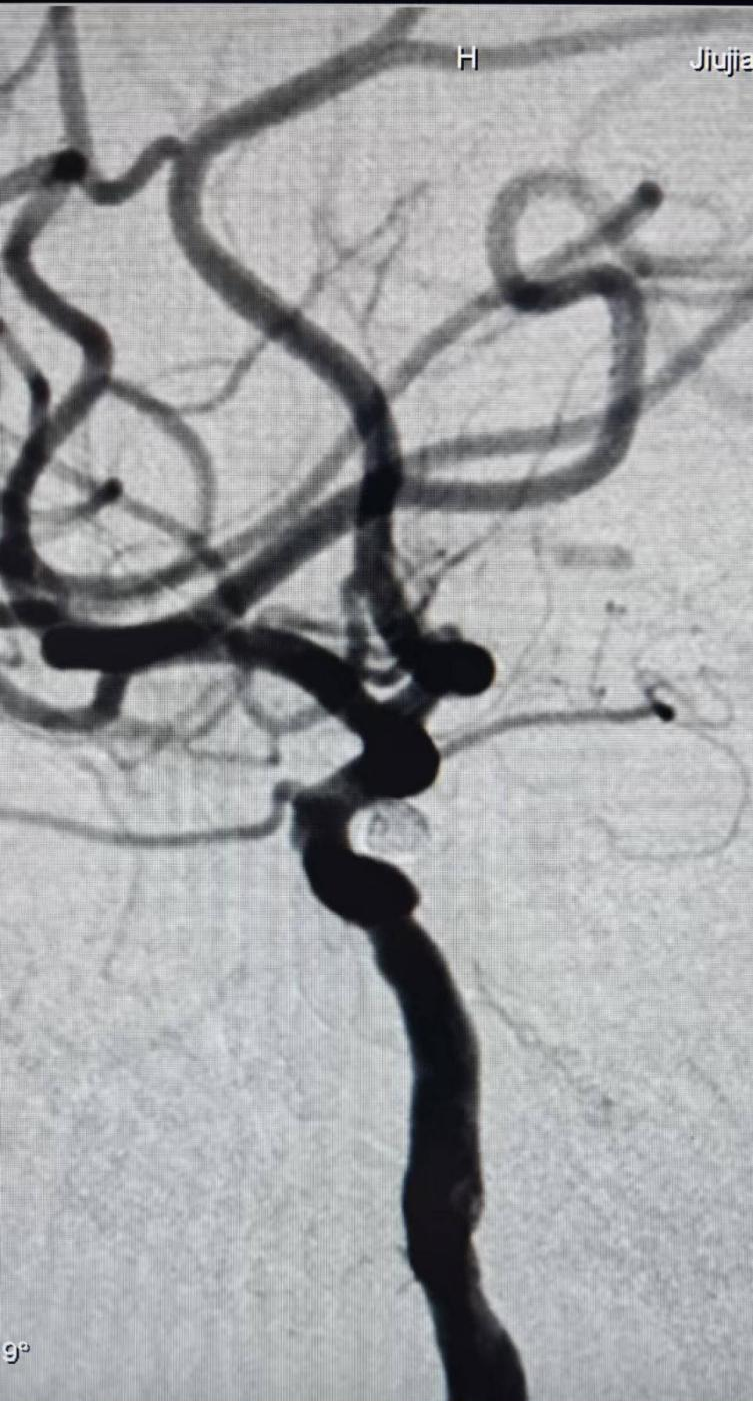

术中,陈进主任团队凭借娴熟精湛的操作技术,将微导管精准送入动脉瘤腔内,依次填入数枚弹簧圈,手术过程十分顺利。术后,李女士恢复迅速,术后第三天便康复出院。

术后DSA造影:右侧颈内动脉C6段动脉瘤不显影,载瘤动脉通畅